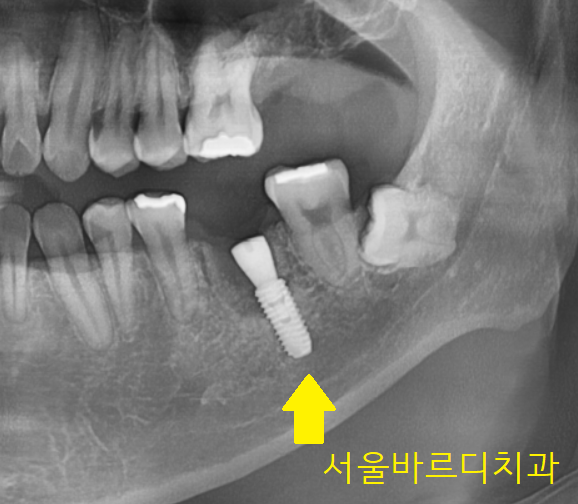

23년 11월 4일 환자분을 처음 보았습니다.

어디가 불편하신지 파악하기 위해

x-ray 사진을 한 장 찍었습니다.

2개 부위가 문제가 보이네요

두개 다 왼쪽 부위가 문제가 있었는데요.

240125

임플란트 수술 후 사진입니다.

왼쪽 위 어금니

왼쪽 아래 치아 모두 발치 후 임플란트가 필요했지만

왼쪽 위 문제가 있는 치아를 발치만 진행

아래부터 수술하고

위에를 진행하기로 하였습니다.